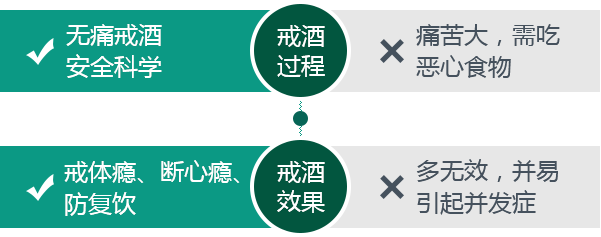

戒酒需谨慎 选对方法是关键

别于普通戒酒医院

治病症/戒体瘾/断心瘾/防复饮

治病症/戒体瘾/断心瘾/防复饮